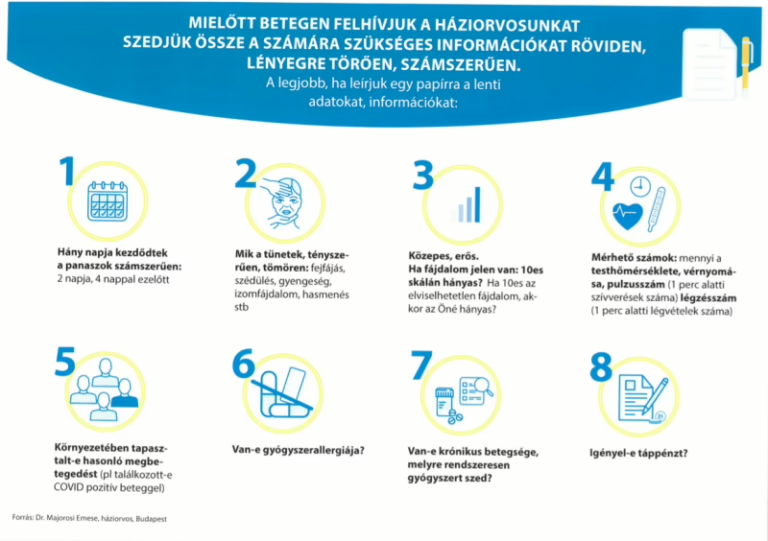

Mielőtt betegen felhívjuk a háziorvosunkat

Mielőtt betegen felhívjuk a háziorvosunkat, szedjük össze a számára szükséges információkat röviden, lényegre törően, számszerűen. Mielőtt betegen felhívjuk.. (pdf)

Mielőtt betegen felhívjuk a háziorvosunkat, szedjük össze a számára szükséges információkat röviden, lényegre törően, számszerűen. Mielőtt betegen felhívjuk.. (pdf)